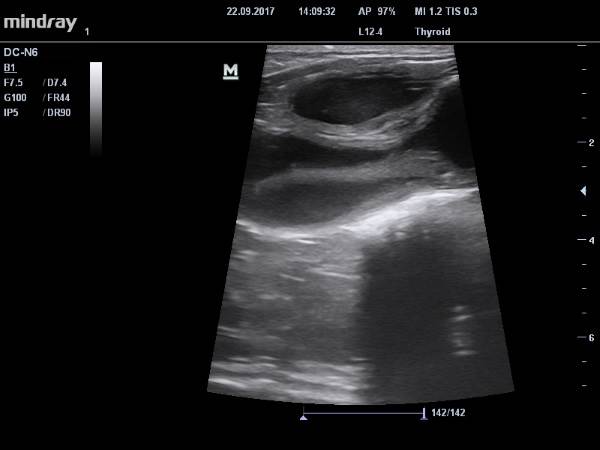

Во всех прочих случаях пиометры у кошек для постановки диагноза пиометра необходимо сочетание ультразвуковой картины :утолщенные, расширенные рога и тело матки,часто с кистозными включениями, наличие полости в матке, заполненной анэхогенным или гипоэхогенным содержимым и цитограммы выделений : множество клеток гноя ( нейтрофилов и макрофагов), бактерий, фагоцитоз.

Видео УЗИ кошке с подозрением на пиометру: